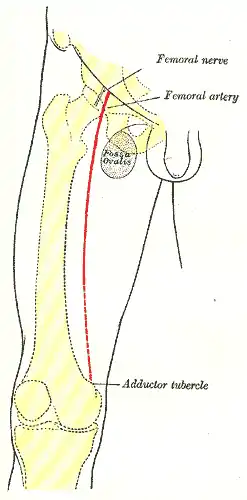

Front of right thigh, showing surface markings for bones, femoral artery and femoral nerve. (Fossa ovalis visible at upper right.) | |

In anatomy, the saphenous opening (saphenous hiatus, also fossa ovalis) is an oval opening in the upper mid part of the fascia lata of the thigh. It lies 3–4 cm below and lateral to the pubic tubercle and is about 3 cm long and 1.5 cm wide.